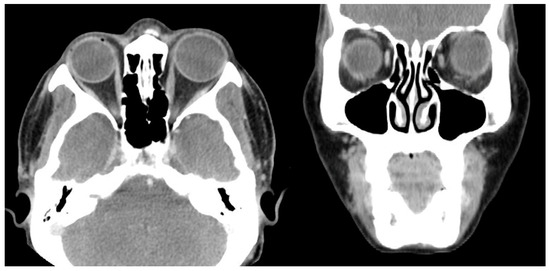

Case 5 was a 67-year-old female who presented with 100 PD ET in the left eye (Figure 5). Her visual acuity was 20/20 in the right eye (SE, −2.125) and hand motion in the left eye (SE, +1.0 D). Twenty years ago, the patient had blunt trauma to her head and lost vision in her left eye. Optic atrophy of the left eye due to traumatic optic neuropathy was observed during the fundus examination. Severe abduction deficit (−4) of the left eye was observed. Preoperative CT was performed and enlarged left medial rectus was noted (Figure 6). During strabismus surgery, severe restriction of the left MR by the forced duction test was noted and the left MR was disinserted accidentally during the procedure. After 1 day, her esodeviation was still 100 PD by MR disinsertion. One month after surgery, esodeviation was 80 PD in her left eye. The patient refused further surgery and was lost during follow-up.

Figure 6. Preoperative CT image of Case 5. Thickening of the left medial rectus muscle with severe left esotropia is noted.